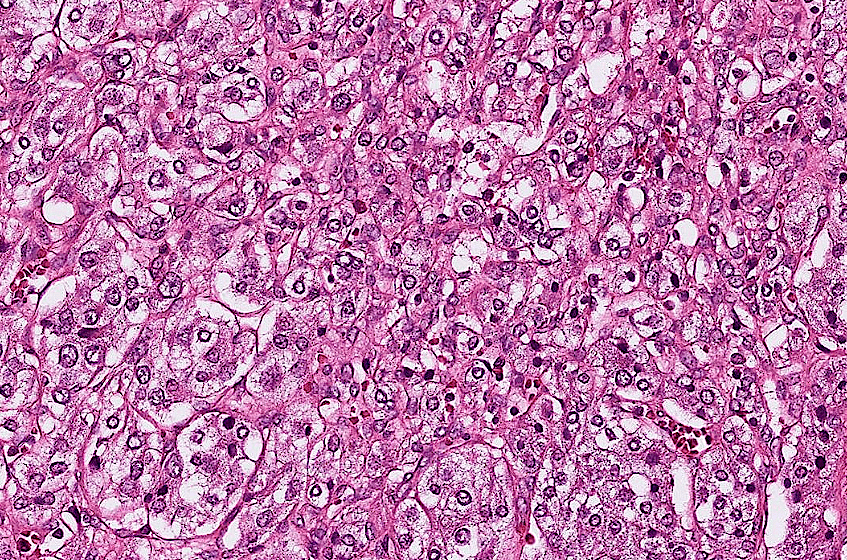

colon cancer